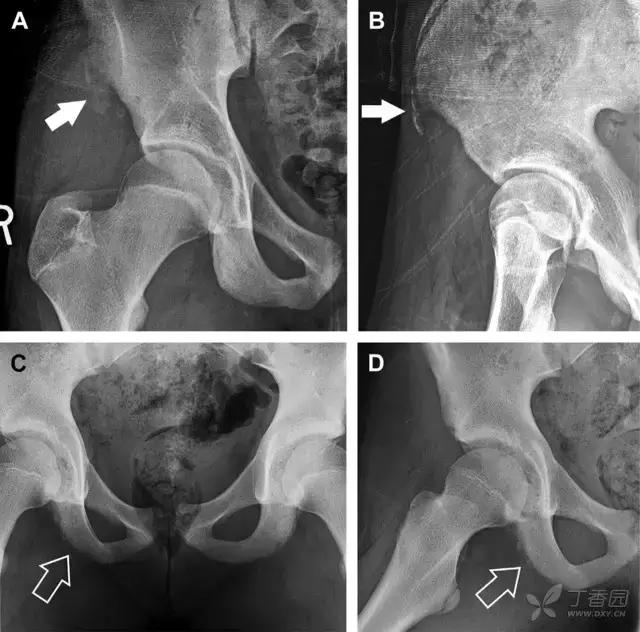

儿童撕脱性骨折

撕脱性骨折常在体育运动时由于肌肉强烈收缩引起。图 4 为容易发生儿童撕脱性骨折的部位。

图 5 儿童撕脱性骨折。正位片(A)和斜位片(B)示从髂前上棘撕脱的骨折碎片(箭头)。正位片(C)和另一个患者的蛙式位片(D)示右侧坐骨支皮质毛糙,腘绳肌腱撕脱损伤(如 C 和 D 空箭头所示)